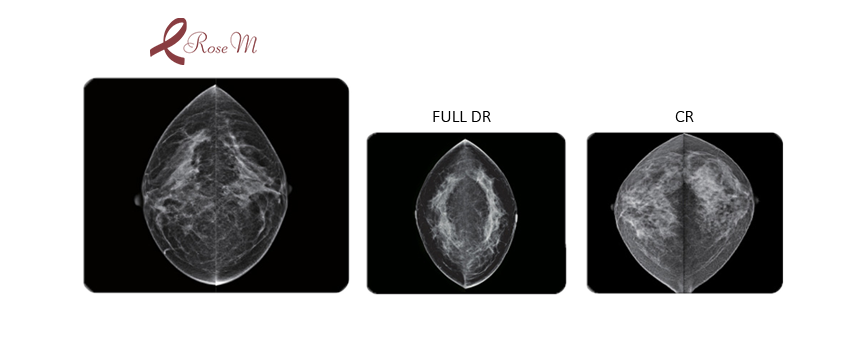

Rose M to pierwszy na świecie kasetowy detektor cyfrowy przeznaczony do systemów mammograficznych, umożliwiający szybką i efektywną konwersję mammografu analogowego do postaci cyfrowej.

Rose M firmy DRTECH zapewnia łatwy i szybki upgrade analogowego mammografu do systemu cyfrowego, gwarantując jednocześnie obraz najwyższej, światowej jakości.